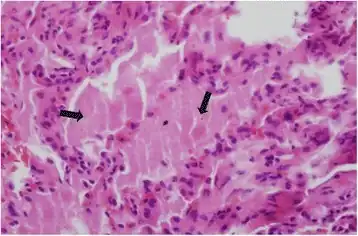

Micrograph of pulmonary alveolar proteinosis, showing the characteristic airspace filling with focally dense globs referred to as chatter or dense bodies. H&E stain.

Lung washings or tissue for histopathologic analysis are most commonly obtained using bronchoalveolar lavage and/or lung biopsy.[12] Characteristic biopsy findings show filling of the alveoli (and sometimes terminal bronchioles) with an amorphous eosinophilic material, which stains strongly positive on PAS stain and the PAS diastase stain. The surrounding alveoli and pulmonary interstitium remain relatively normal.[13] Electron microscopy of the sample, although not typically performed due to impracticality, shows lamellated bodies representing surfactant.[14] An alternative diagnosis with similar histomorphologic findings is Pneumocystis jirovicii pneumonia.[14]

Lung washings characteristically yield a fluid which is "milky"composition. Under the microscope, samples show 20-50 micrometer PAS-positive globules on a background of finely granular or amorphous PAS-positive material. There is typically a low numbers of macrophages and inflammatory cells (although this is variable).[13][14]